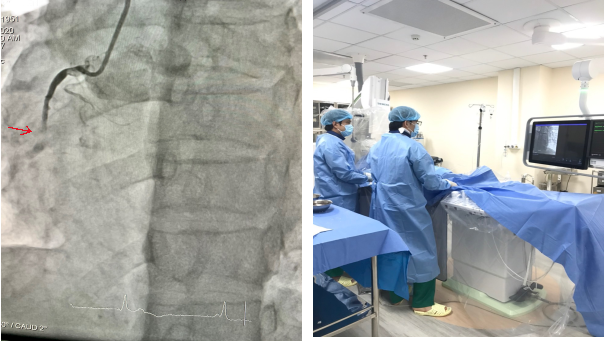

CẤP CỨU THÀNH CÔNG BỆNH NHÂN NHỒI MÁU CƠ TIM CẤP

Ngày 17 tháng 5 năm 2022, Bệnh viện đa khoa tỉnh Hòa Bình tiếp nhận bệnh nhân nam, 62 tuổi, nhập khoa Hồi sức cấp cứu trong tình trạng đau dữ dội vùng ngực ...